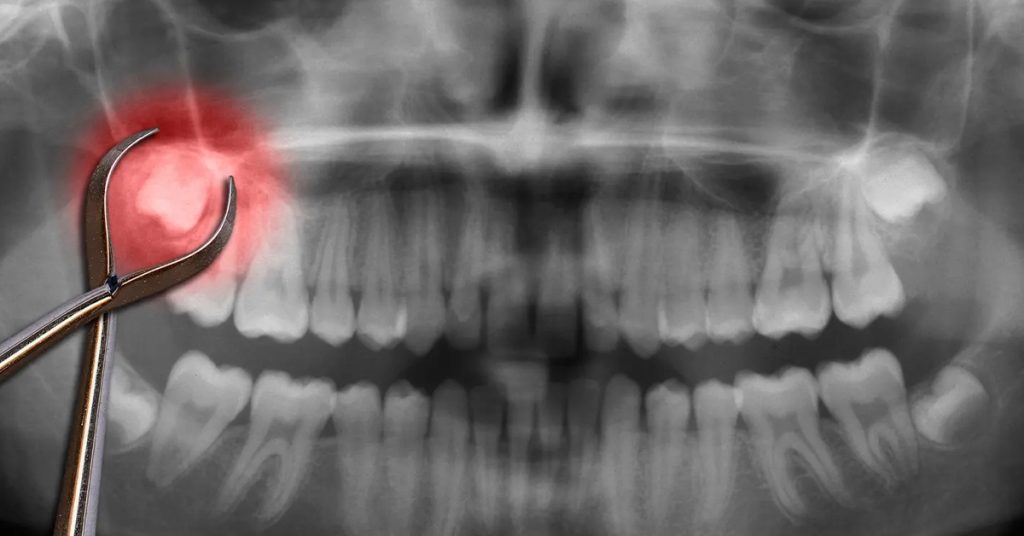

Why Post-Surgery Care Matters Wisdom tooth removal is a common procedure, but proper aftercare is crucial to ensure smooth healing […]